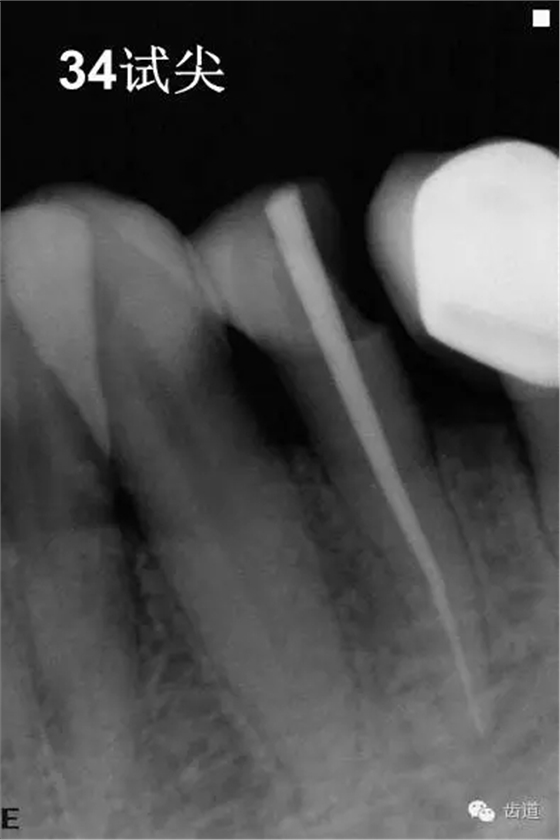

4、34常規(guī)根管治療。(2013年8月)

3、34術(shù)前片顯示遠中面暗影近髓